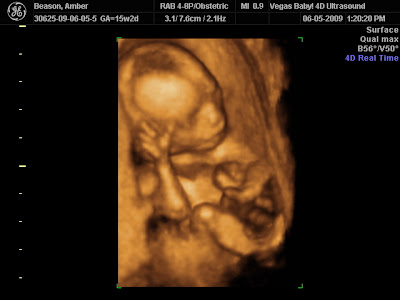

26 weeks and up…HD LIVE 4 PACKAGE. 3D pictures are still pictures of your baby in three dimensions. Picture 3 is a 4D ultrasound of a fetus at 15 weeks pregnancy.

15 Week gender 3D ultrasound. Picture 1 shows a fetus at 15 weeks and 4 days. 15 weeks is early even for a 3d ultrasound.